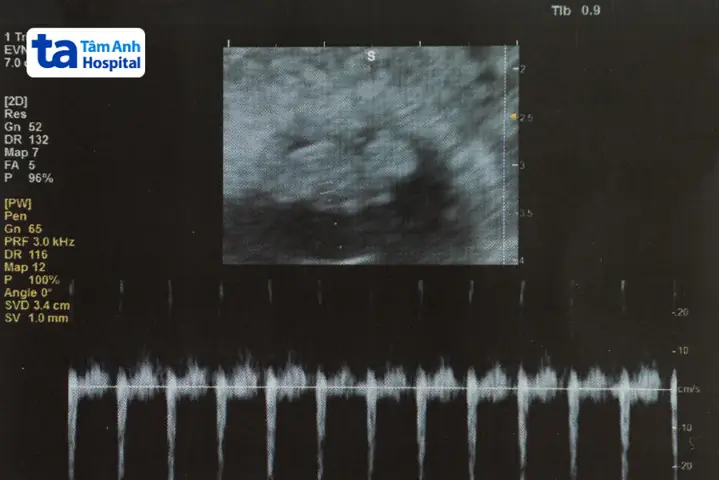

Khi siêu âm ở tuần thai thứ 7, bác sĩ sẽ đo một số thông số quan trọng để đánh giá sự phát triển của thai nhi. Các thông số chính bao gồm:

- CRL (Crown-Rump Length): Chiều dài đầu mông, đo từ đỉnh đầu đến mông thai nhi

- BPD (Biparietal Diameter): Đường kính lưỡng đỉnh của đầu thai nhi

- HC (Head Circumference): Chu vi đầu thai nhi

- AC (Abdominal Circumference): Chu vi bụng thai nhi

Theo Hiệp hội Sản phụ khoa Việt Nam, kích thước phôi thai 7 tuần tuổi tiêu chuẩn có CRL trung bình từ 10-12mm. Tuy nhiên, mỗi thai nhi có tốc độ phát triển khác nhau, vì vậy các thông số này có thể dao động trong khoảng 8-14mm là bình thường.

Siêu âm là phương pháp chính để theo dõi kích thước phôi thai 7 tuần tuổi. Hiện nay có hai phương pháp siêu âm phổ biến:

Siêu âm đầu dò âm đạo: Được khuyến nghị thực hiện ở tam cáng đầu vì cho hình ảnh rõ nét hơn, đặc biệt khi thai còn nhỏ. Phương pháp này giúp bác sĩ đánh giá chính xác kích thước phôi thai, tim thai và vị trí làm tổ.

Siêu âm qua thành bụng: Thường được thực hiện khi thai lớn hơn (từ 12 tuần trở đi). Tuy nhiên, ở tuần thứ 7, siêu âm qua thành bụng có thể không cho hình ảnh rõ ràng bằng đầu dò âm đạo.

Một trong những dấu hiệu quan trọng nhất cho thấy thai nhi đang phát triển bình thường là tim thai. Ở tuần thai thứ 7, tim thai đã có thể được phát hiện qua siêu âm với nhịp đập khoảng 100-160 lần/phút.

Tim thai đều, mạnh là dấu hiệu cho thấy thai nhi đang phát triển khỏe mạnh. Nếu tim thai yếu hoặc không đều, bác sĩ có thể yêu cầu theo dõi thêm để đánh giá tình trạng thai nhi.